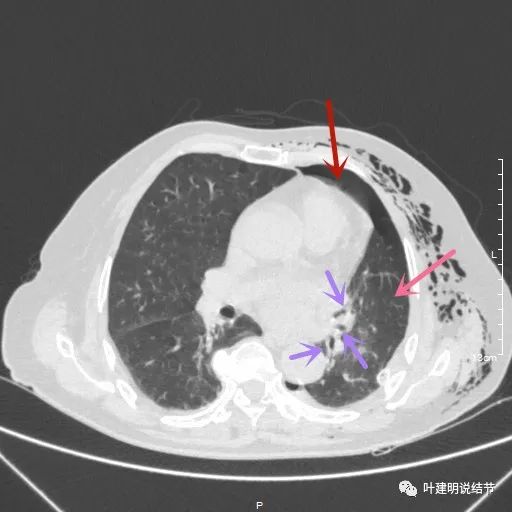

术后第二天患者乏力纳差,起不了床!而且CRP也大于100,我们的神经又紧张起来,怕支气管胸膜瘘,怕感染、怕有并发症发生。还好化验后是低钾,予以补充钾与镁2天后胃纳与精神均有明显改善,我们再加用静脉高营养支持治疗,补充白蛋白,情况逐渐好转。我们也于术后第4天查了CT,发现如下:

下叶膨胀良好

下叶膨胀良好,上叶残腔不大

下叶膨胀良好,上叶残腔不大,蓝色箭头示左主支气管

下叶膨胀良好,上叶残腔不大。桔色箭头示吻合口处,通畅

以上图像示下叶膨胀良好,上叶残腔不大,紫色箭头示吻合口以远的支气管通畅,肺膨胀佳